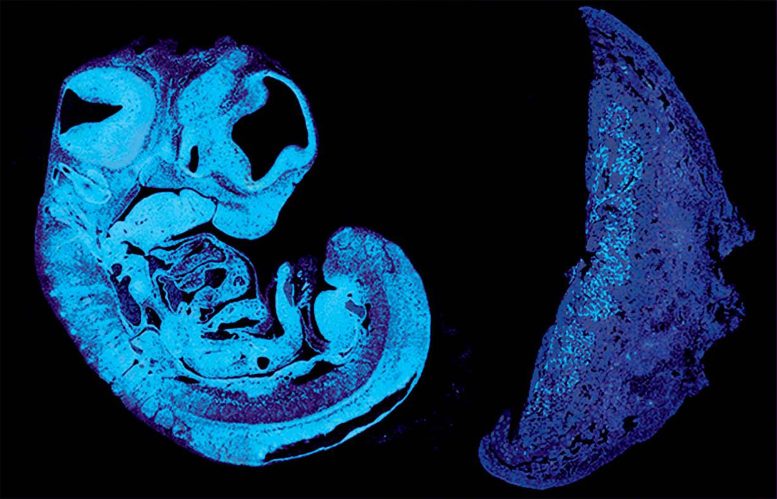

剑桥大学的科学家们发现了胎儿用来控制胎盘营养供应的一个关键信号,揭示了遗传自父亲和母亲的基因之间的一场拔河战。这项在小鼠身上进行的...